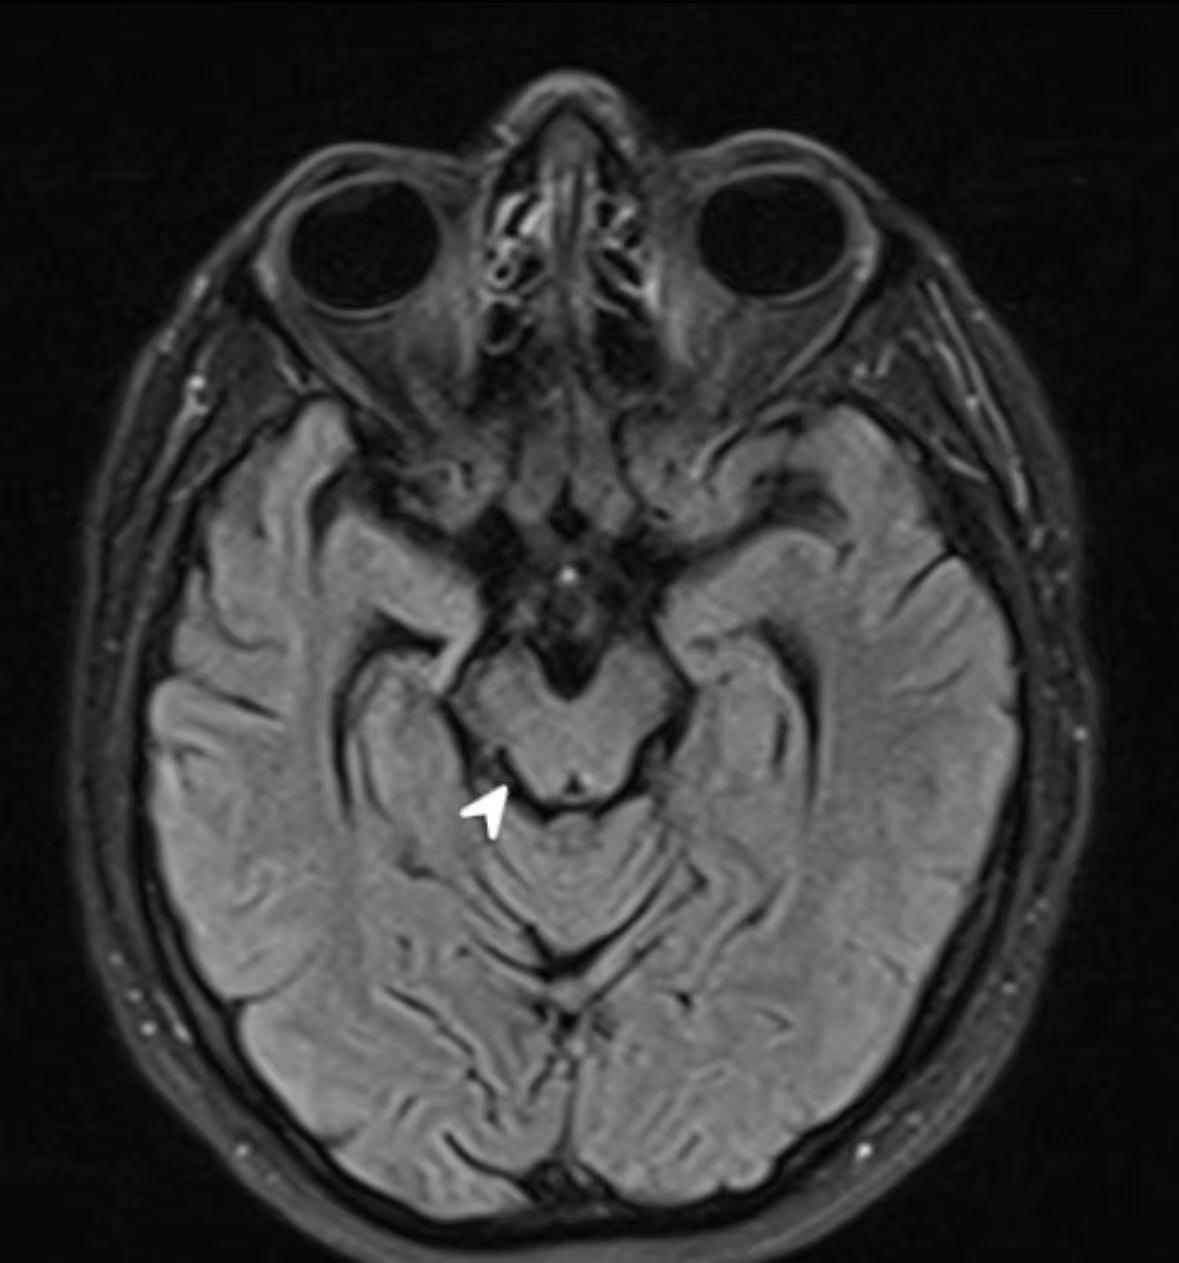

头颅MRI提示:脑内多发缺血灶:脑萎缩(弥漫性的皮质萎缩,中脑上缘凹陷)。

1.病例主要特点 (1)老年男性,慢性病程。 (2)头晕伴走路不稳5年,饮水呛咳3年,视物模糊1年。 (3)主要阳性体征:双眼球居中,无突出、凹陷,各向运动有受限,尤其向上下、右侧运动时眼球明显受限,双眼水平眼震(+),双侧瞳孔等圆等大,直径约2.0mm,双侧直接、间接对光反射存在;声音嘶哑、构音障碍,偶有饮水呛咳、吞咽困难:起步困难,行走身体易后仰;左侧掌颌反射阳性。 (4)头颅MRI提示:脑内多发缺血灶;脑萎缩。

(5)血液、脑脊液、脑电图等辅助检查可无异常发现.头颅CT可见脑室轻度扩大,MRI可显示中脑萎缩和脑干被盖部T2加权像弥散性高信(影像表现:弥漫性皮质萎缩,中脑上缘凹陷,似“蜂鸟征”,中脑基底萎缩导致大脑脚之间间距变宽,似“米老鼠征”)。